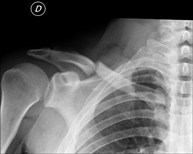

- Limb X-ray

This technique uses X-ray imaging to examine the limbs, especially the bones. Indicated for: trauma, joint infections.